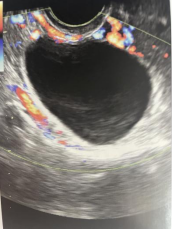

B超是诊断LUFS最好的方法,通常排卵的超声表现为:排卵前成熟卵泡消失、皱缩且体积较原来缩小一半以上;或直肠子宫陷窝可见游离液体,若卵泡黄体过渡期B超未提示排卵且黄体中期孕酮水平>3ng/ml,即可诊断LUFS。

卵泡黄素化囊肿超声图